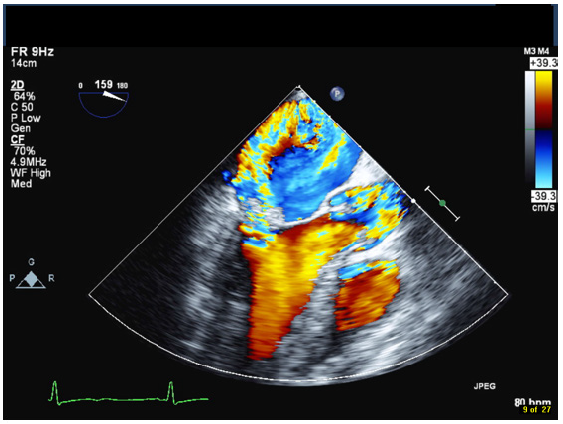

A 42-year-old male with a history of chronic nephrolithiasis presented to the hospital after neighbors found him unconscious at home. On initial evaluation, he was febrile (38.9) with blood pressure of 120/104mmHg. He was severely hypoxic with a sinus rate of 90 beats/minute. His examination revealed multiple abrasions, and he was minimally responsive with a holosystolic murmur at the apex. His electrocardiogram showed normal sinus rhythm with no acute ST-T wave changes. Laboratory data revealed a white cell count of 17.4/nl, platelet count of 109/nl, lactate level of 4.8 mmol/l and creatinine of 1.57mg/dl. Computed tomography of the head revealed multiple regions of acute infarction involving the right inferior cerebellum, left occipital lobe with mass effect on the left occipital horn. He underwent a transthoracic echocardiogram that showed vegetations on both the mitral and aortic valve. He underwent a trans-esophageal echocardiogram, which demonstrated multiple vegetations on the mitral (Figure 1), aortic (Figure 2) and pulmonic valves (Figure 3) with severe pulmonic, mitral and aortic insufficiency (Figure 4 & 5). Despite negative urine cultures, serial blood cultures grew Aerococcus urinae and he was given appropriate IV antibiotics. He was evaluated for possible valvular surgery and was deemed to be a poor surgical candidate. He later developed splenic and renal infarcts followed by significant hemodynamic instability requiring vasopressors and ultimately succumbed to his illness after he developed multi organ failure and disseminated intravascular coagulation.